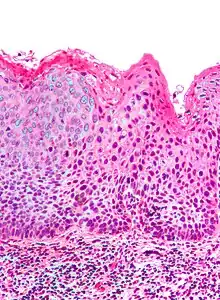

| Micrograph of (classic) vulvar intraepithelial neoplasia III. H&E stain. | |

Micrograph of vulvar intraepithelial neoplasia III. H&E stain.